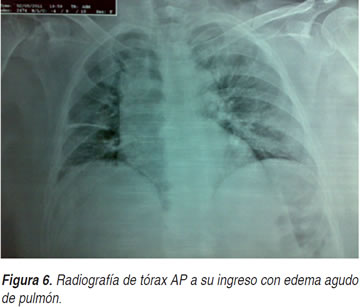

CASE REPORT Tubular Aggregate myopathy Presenting With Acute ...

Tubular aggregate myopathy presenting with acute type II respiratory failure and severe orthopnoea undiagnosed COPD was made by the admitting doctors and the patient was treated with bronchodilators and controlled oxygen therapy. However, ... Doc Viewer